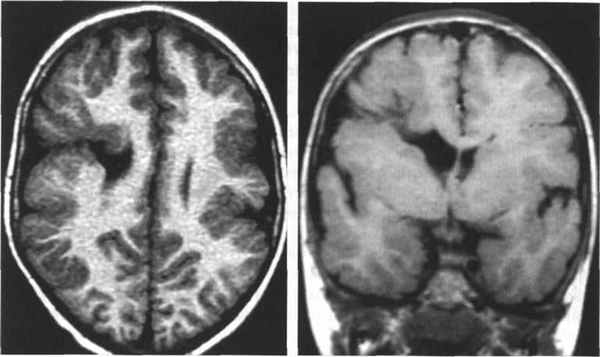

МРТ. Т1-зависимая корональная томограмма. Агирия.

МРТ. Т1-зависимая аксиальная томограмма. “Двойная кора”.

Классическая (тип I) лиссэнцефалия.

Т1-взвешенная аксиальная МРТ: (мутация LIS I) толстая корковая лента с гладкой поверхностью и прямой, неволнистой границей между серым и белым веществом.

Обратите внимание на присутствие нескольких мелких борозд в лобной области и полное отсутствие борозд сзади,

отсутствие оперкуляции с широко открытой сильвиевой бороздой и слоистость коры со слабой границей между гетеротопированными и полностью мигрировавшими нейронами.

Субкортикальная групповая гетеротопия («двойная кора»):

(а) Аксиальный срез МРТ: широкие, непрерывные группы с таким же сигналом как от коры.

(б) Коронарный срез: в этом же случае имеется расширение желудочков преимущественно спереди.

(в, г) MPT, Т1-взвешенная последовательность — (в) аксиальный срез, (г) сагиттальный срез -тонкий слой белого вещества, лежащий между истинной корой и тонкой линейной гетеротопией серого вещества (стрелки).